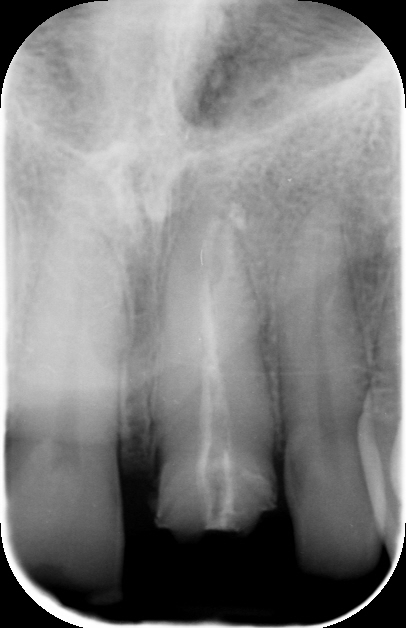

Trattamento endodontico inadeguato: Il trattamento canalare precedente non era stato eseguito correttamente, rendendo il dente suscettibile a ulteriori complicazioni.

Ritrattamento endodontico: È stato eseguito un nuovo trattamento canalare per assicurare la corretta sigillatura del sistema radicolare, eliminando eventuali infezioni residue e garantendo la longevità del dente.

1. Ritrattamento endodontico:

Il primo passo è stato rimuovere la vecchia otturazione canalare e ritrattare i canali radicolari, assicurando una pulizia accurata e la successiva otturazione tridimensionale per prevenire future complicanze.